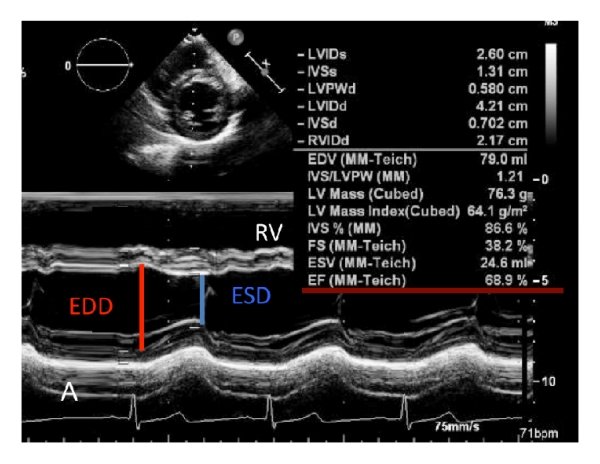

4.Echo is likely to show more of a Global hypokinesia rather than specific coronary territory